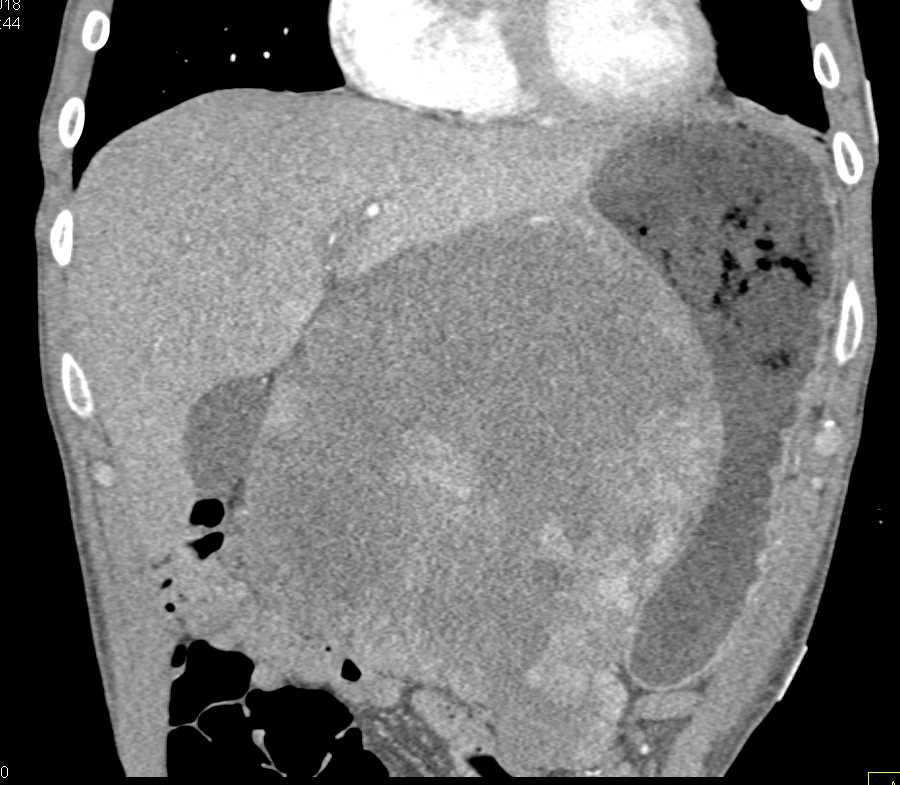

Lagre Gastric GIST Tumor